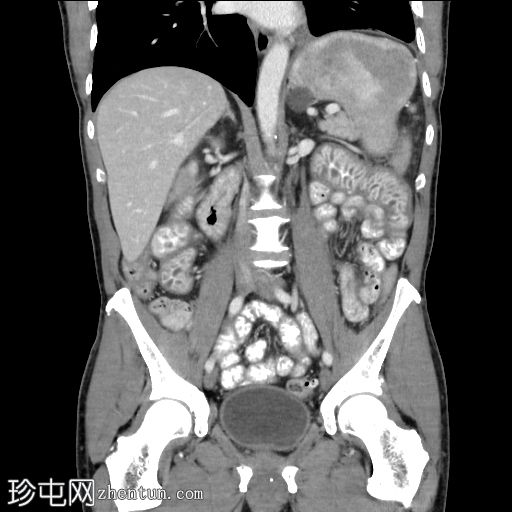

轴向C+门静脉期

冠状C+门静脉期

十二指肠和空肠皱襞弥漫性低衰减结节性增大增厚,

造影剂(阳性)增强。微量腹水。

左侧少量积液,伴轻度胸膜增厚。良性肾脾囊肿。骨髓异质性。

这是酪氨酸激酶抑制剂 (TKI) 相关小肠淋巴管扩张的典型表现,是癌症再分期时需要注意的独特副作用。此类药物可导致小肠和大肠淋巴管扩张,从而引起胃肠道症状。